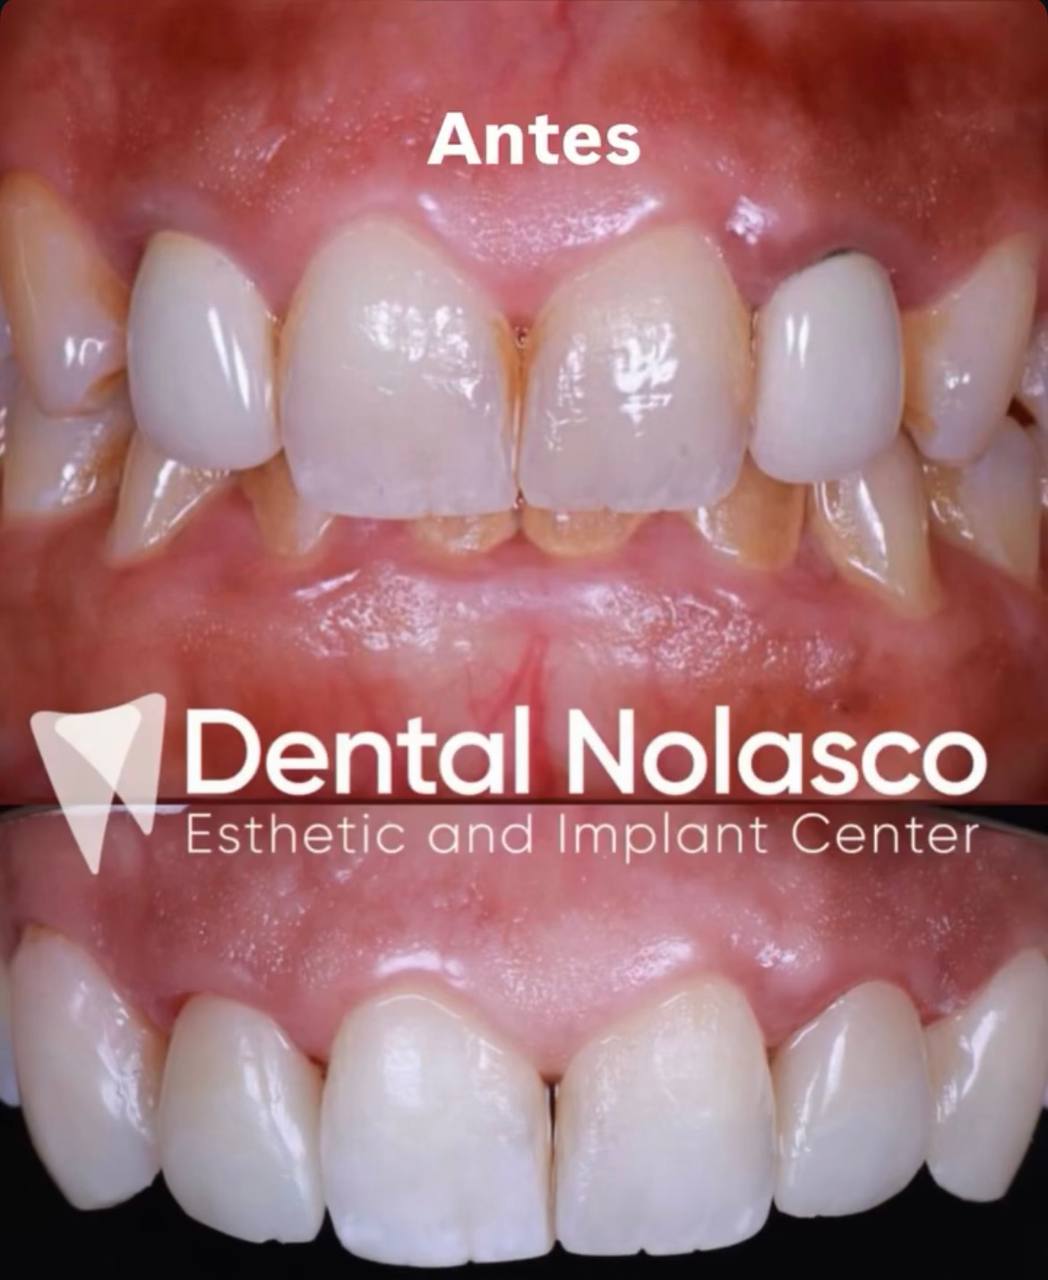

Estética Dental

Transforma tu sonrisa con tratamientos diseñados para resaltar tu belleza natural. Ofrecemos blanqueamientos, carillas y remodelación dental para lograr una sonrisa armónica, saludable y atractiva.